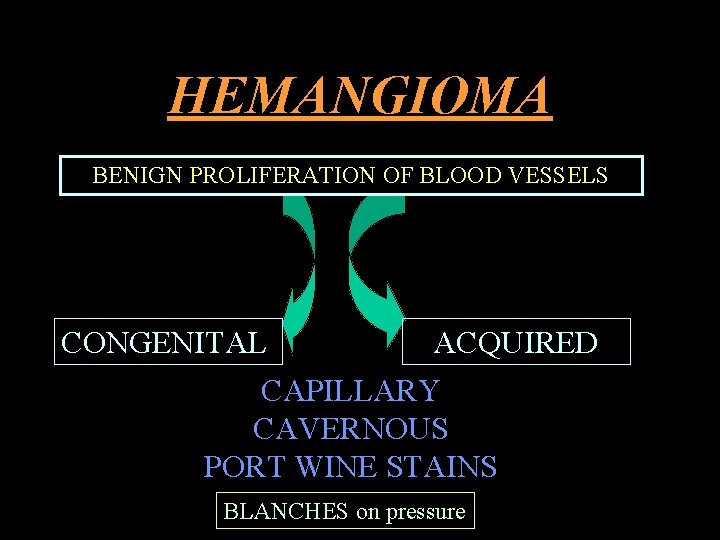

HEMANGIOMA BENIGN PROLIFERATION OF BLOOD VESSELS CONGENITAL ACQUIRED CAPILLARY CAVERNOUS PORT WINE STAINS BLANCHES on pressure